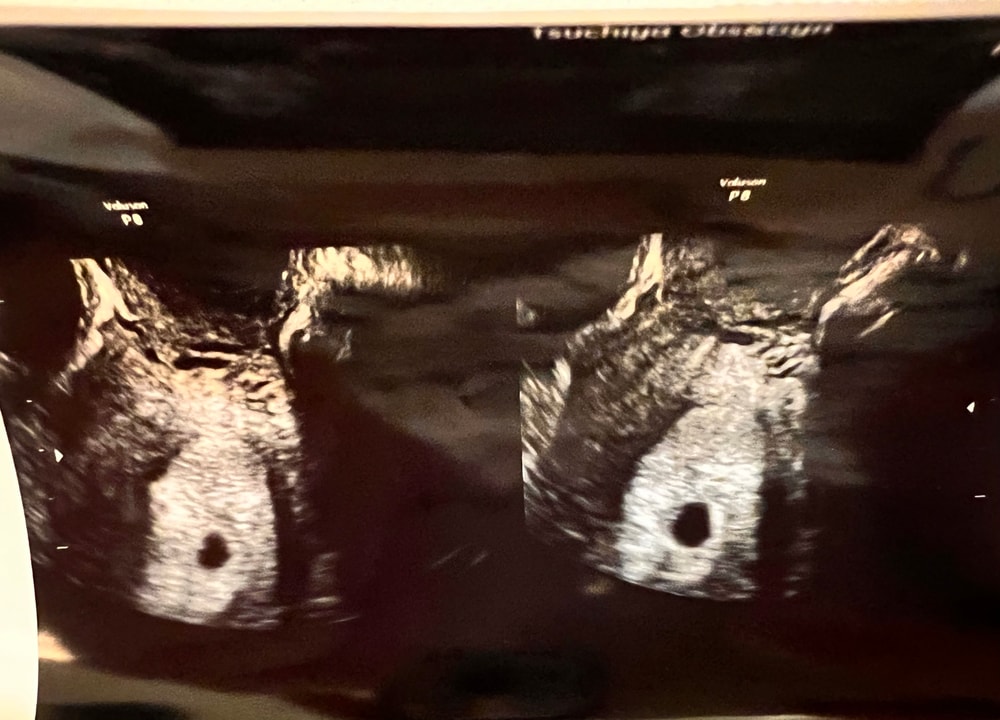

УЗИ 5 недель и 2 дня 28 ДПО

Страхи, переживания и немножечко нытьяСегодня я была на УЗИ. По месячным срок совсем маленький - 5 недель и 2 дня. По овуляции - 28 ДПО (овуляция была на 13 день цикла). Подтвердили, что беременность маточная. Это уже огромное счастье и надежда. Но врач не увидел эмбриончика… даже не сказал размер плодного яйца. И тут я заволновалась. Назначили узи контроль через неделю. И тут меня накрыла паника .